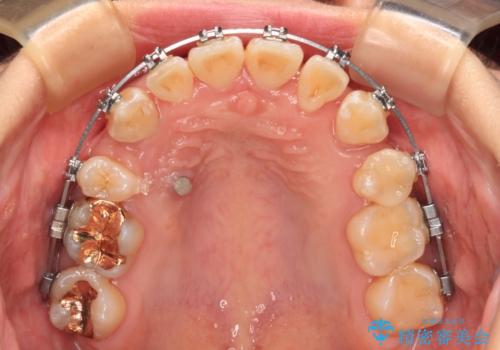

- 矯正装置

- メタルブラケット

上顎は左右の第一小臼歯2本を、下顎は左右第二小臼歯2本を抜歯することで、奥歯の咬み合わせを改善しながら、デコボコを解消していくこととしました。

奥歯の咬み合わせ改善にはどうしても長期間を要します。

3年強とお伝えしておりましたが、予想通り3年3ヶ月で治療を終えることができました。